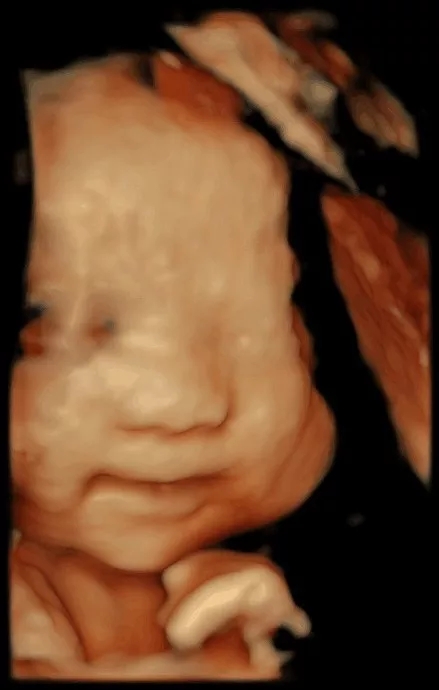

“妈妈,您知道吗?

与您紧密相连的日子里我喜欢您轻轻抚摸肚子,听着您为我精心准备的音乐,每一天,当您睡醒的时候第一次叫我宝贝,当您遇到了开心的事情而开怀大笑,当您去练瑜伽,去看风景,当您遇到美好人和事物时,去做您喜欢做的每一件事,我都会发自内心地和您一样觉得开心。

对我来说,只要一想到您,我就情不自禁地想笑,只要一想到能做您的宝贝我就好幸福。”